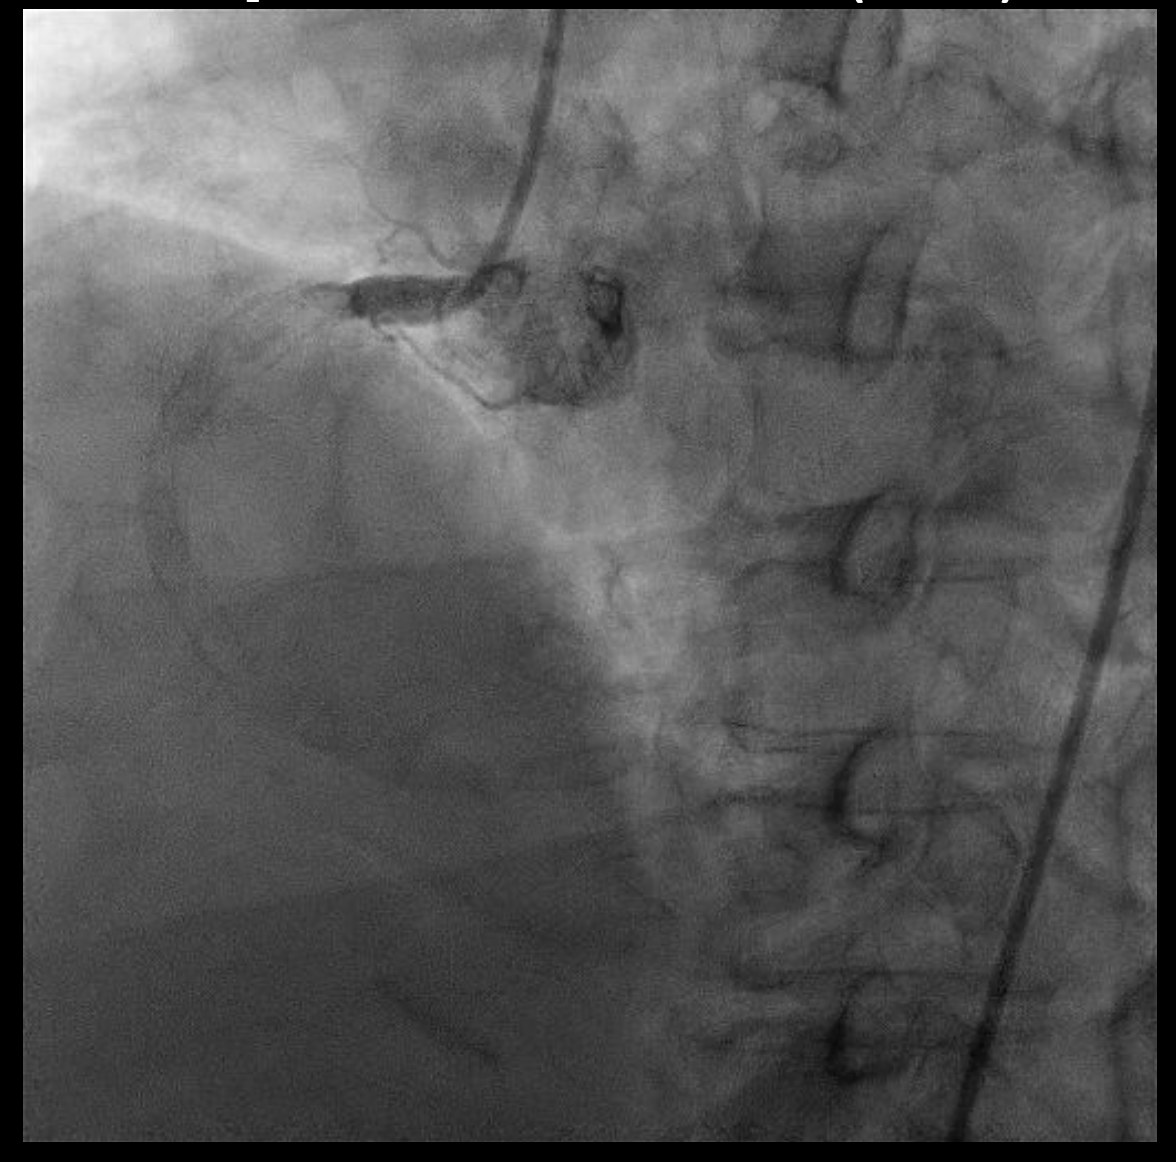

Dominant RCA with heavy calcification, total occlusion at RCA due to extending thrombus from the proximal to the distal segment of the RCA (TIMI grade 0 flow). LM and LCx were normal. LAD was normal except for myocardial bridging at its mid portion.

Via transfemoral access, initial attempts to advance a guidewire to the distal vessel were unsuccessful. To facilitate better guiding support, an anchor-wire technique was employed by placing a guidewire in a RV branch. Subsequently, a guidewire was successfully advanced across the occlusion into the PDA. Initial pre-dilatation was performed sequentially with 1.5 mm and 2.0 mm SC balloons. Subsequently, the intervention was escalated using larger 2.5 mm to 3.0 mm NC balloons to dilate the segment from the proximal to the distal RCA.Following two unsuccessful conventional thrombus aspirations, TIMI 0 flow and Grade V thrombus burden persisted despite intracoronary epinephrine administration at distal RCA via thrombo-suction catheter. The patient developed profound hemodynamic instability (BP 60/49 mmHg) refractory to vasopressor support. We therefore decided to rapidly employ the guiding catheter (BL 3.5/5F) as a large-bore aspiration device despite the inherent risk of vessel injury. The catheter was advanced with the support of an anchor balloon. The guiding catheter was connected to a 3-way manifold and a balloon inflation device. Using negative pressure, it was advanced to the distal RCA for direct thrombus aspiration. This maneuver was repeated once, achieving successful thrombus extraction.Following thrombus removal, the vessel was prepared with a 3.0 mm NC balloon. A 4.0 ¡¿ 24 mm drug-eluting stent was then implanted in the mid RCA.

We present a case of inferior STEMI with high thrombus burden with total RCA occlusion identified as the culprit lesion. Following catheter-guided thrombectomy using a BL 3.5/5 F catheter, the patient achieved complete revascularization and significant improvement in RCA flow. The target vessel reached optimal stent expansion with restoration of TIMI grade 3 flow and no complications.